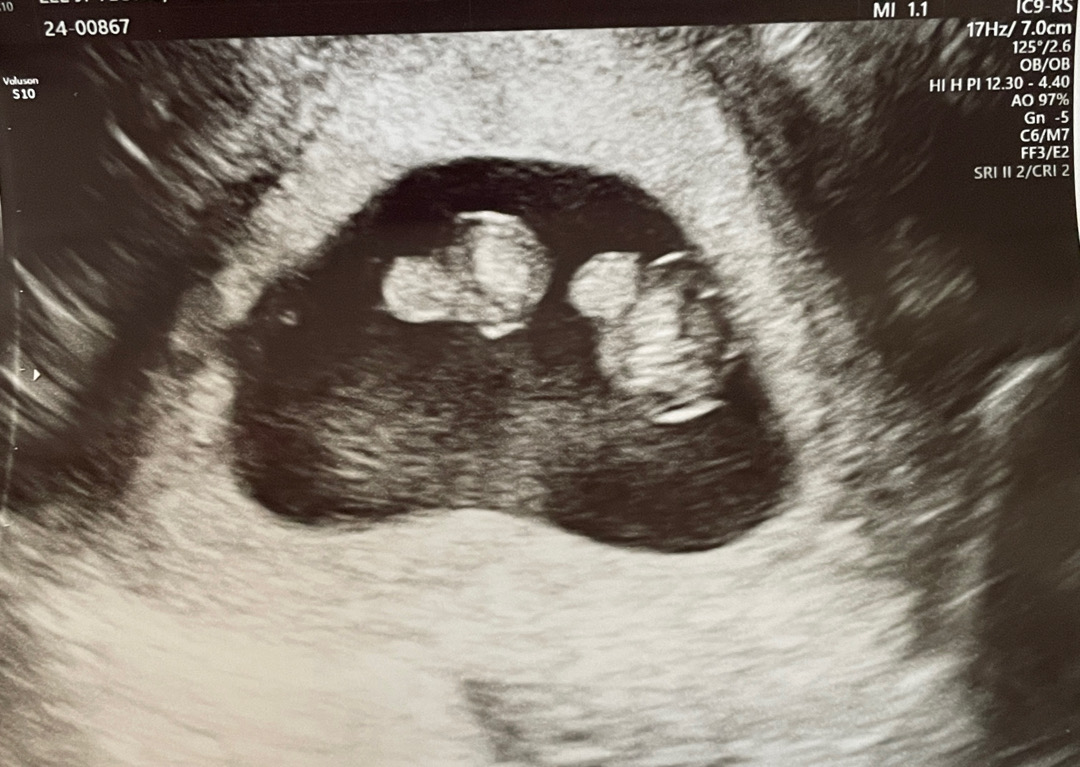

7주3일차 일란성쌍둥이 초음파 심장소리

심장이 둘다 100은 넘는데 40bpm차이가 나네요??? 산넘어 산.. 그래도 저번주보단 크기가 많이 컸으니까 위안을 삼아봅니다..